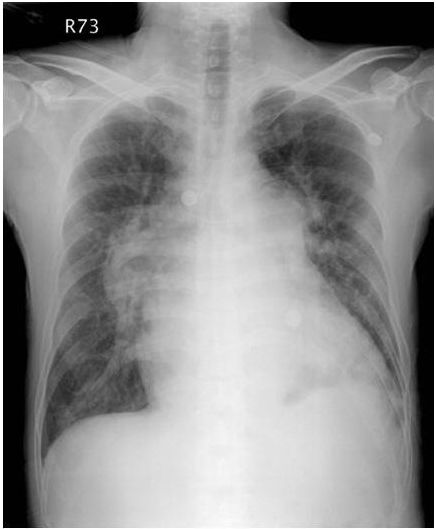

17. 60歲男性,患有糖尿病及肺氣腫,因嚴重社區型肺炎併發急性呼吸窘迫症候群及呼吸衰竭插管住進加護病房。住院十天後,情況逐漸穩定,但偶爾會躁動及咳嗽。體溫 37.5℃, 血壓 115/70 mmHg, 心速率 90/min, 規則, 呼吸速率 22/min, SaO2 94% (使用 Fi O2 70% , pressure control mode, PEEP 14 cm H2O, plateau pressure 34 cm H2O)。隔日早上護士小姐緊急通知病人突然意識喪失,四肢發紺,血壓60/30 mmHg , 心跳突然增快到150/min : 體溫38℃, 呼吸速率35/min, 呼吸音微弱,呼吸器呈現 high pressure alarm, 即使以ambu bagging 也很難將氧氣送入。此病人之休克最有可能是下列哪一種?

(A) 肺動脈栓塞併阻塞性休克。 (B) 心肌梗塞併心因性休克。 (C) 肺炎惡化併敗血性休克。 (D) 張力性氣胸併阻塞性休克。 (E) 心室上頻脈併心因性休克。